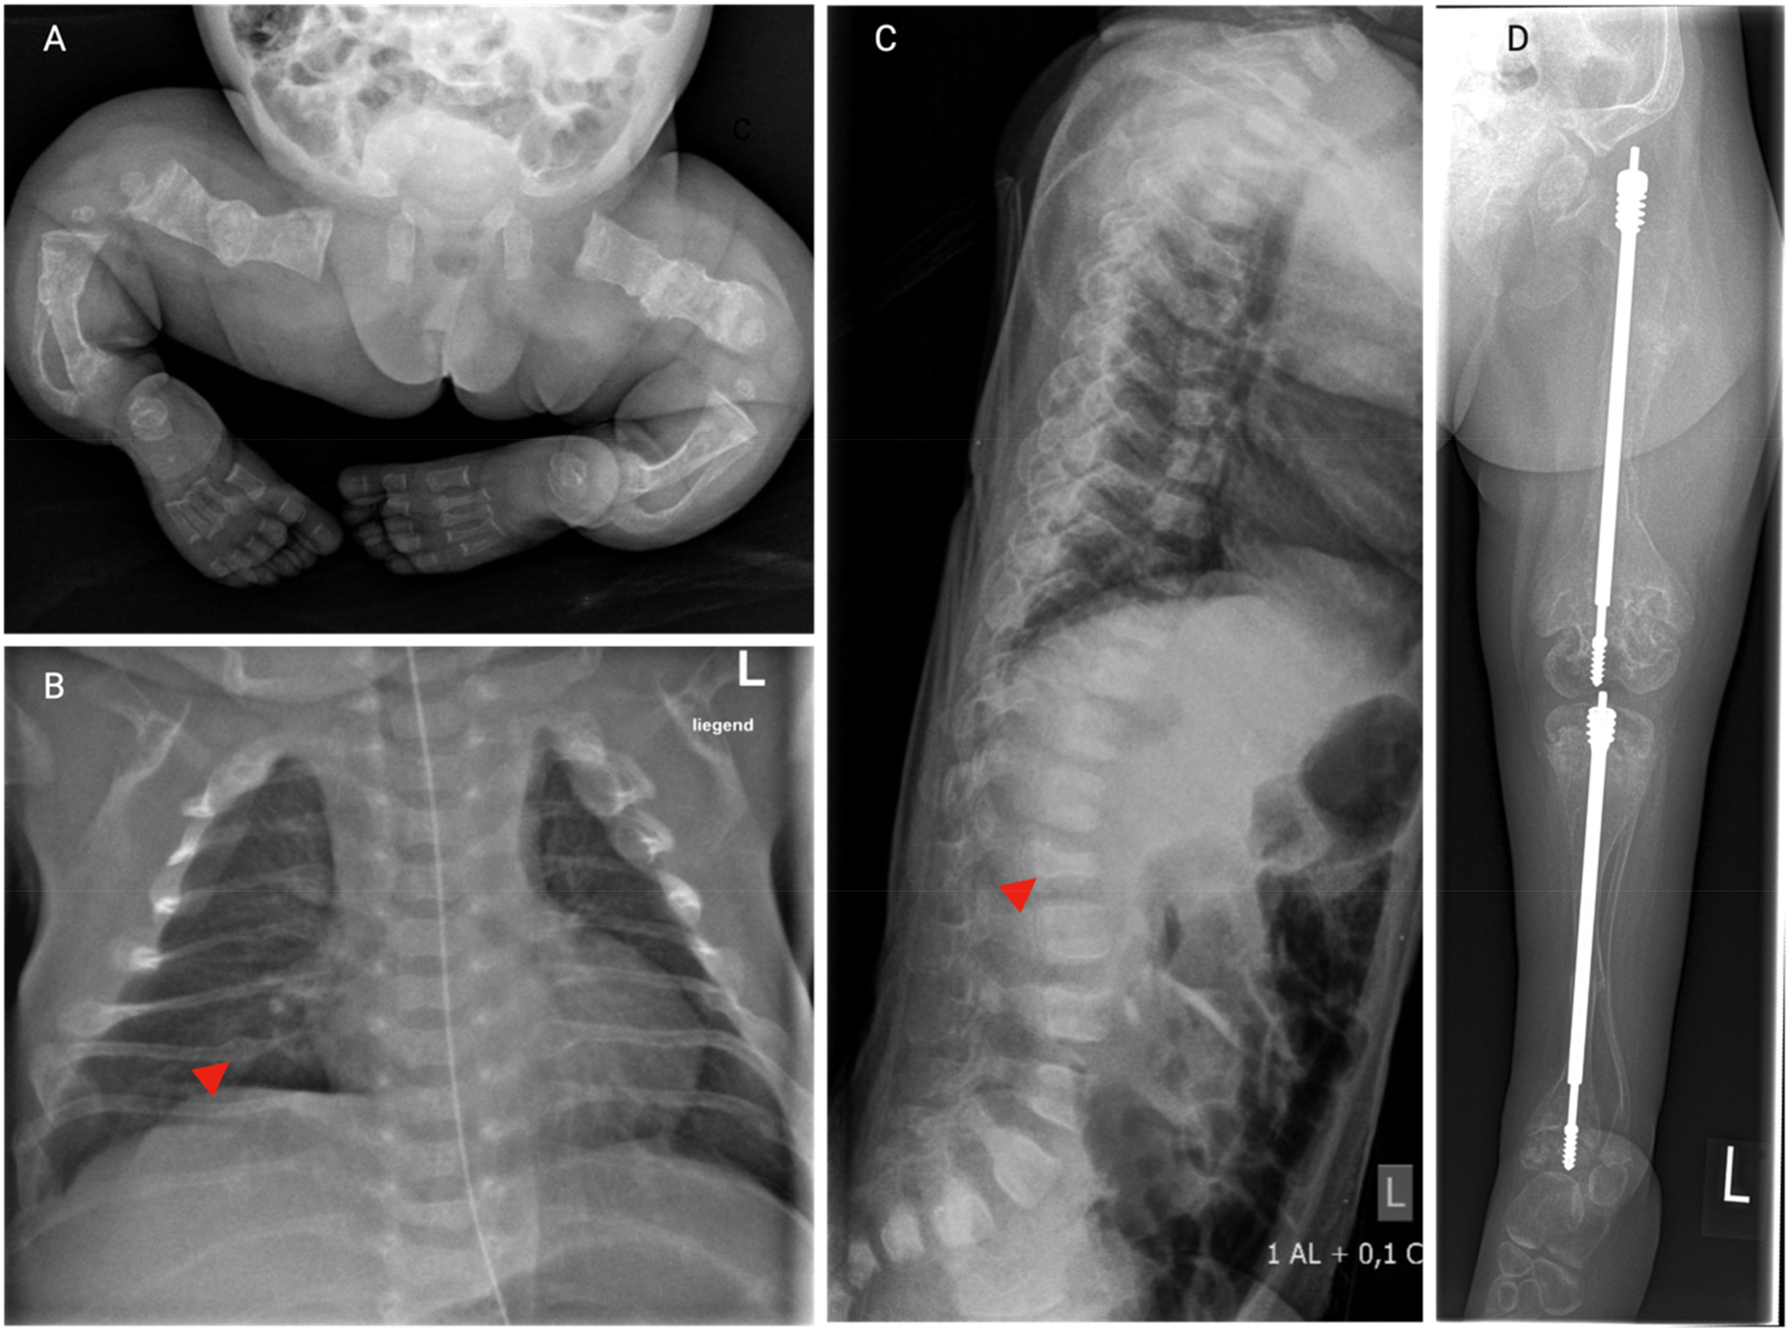

Fractures occur typically in the long bones of the upper and lower extremities as well as in vertebrae and can lead to severe skeletal deformities, such as bowed limbs and scoliosis (Figure 1). Thorax deformities can restrict lung expansion and impair respiratory function [67]. In severe cases, scoliosis may cause neurological complications due to compression of the spinal cord [68], 69]. Basilar invagination is a condition more commonly observed in severe forms of OI, where recurrent microfractures cause the skull base to flatten, leading to spine migration into the skull [70]. This can compress the brainstem and cerebellum, causing hydrocephalus due to disrupted cerebrospinal fluid circulation and cranial nerve damage. Early screening for new neurological symptoms is crucial. Growth is often affected due to disruptions in the growth plates, reflecting the disease’s profound impact on bone development [71]. Repeated immobilization following fractures contributes to muscle atrophy and secondary bone loss, further aggravating bone fragility. Chronic pain is often underrecognized by parents and caregivers and consequently insufficiently managed [72]. This significantly impacts quality of life in children and adolescents with OI, as highlighted by the recently published IMPACT survey, which documented experiences of individuals with OI and their caregivers [73], 74].

Skeletal manifestations of OI. Series of X-rays from a young girl with severe OI type VIII. (A) X-ray of the lower body 3 days after birth showing multiple healed fractures, generalized osteopenia, bowing and shortening of the long bones. (B) Chest X-ray 3 days after birth. Notice the thin rips with irregularly shaped, thickened areas (arrow head) consistent with healed fractures. (C) Lateral X-ray of the spine in the age of 1.5 years reveals flattened, irregularly shaped vertebral bodies (arrow head), indicative of compression fractures, along with pronounced kyphosis. (D) X-ray of the lower extremity in the age of 5 years after surgical insertion of telescopic nails in the tibia and femur. Notice the generalized osteopenia, thin cortical bones, multiple fractures in the tibia and femur, and bowing of the thin fibula. The distal metaphyses of the femur appear wide and irregular.